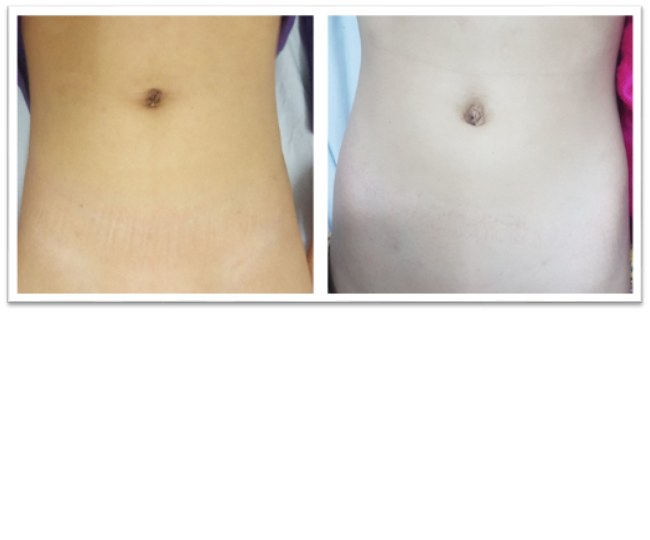

Hình ảnh lỗ thoát vị bẹn trước (A) và sau (B) đóng với phẫu thuật nội soi 1 lỗ.

Cho đến nay thì phẫu thuật nội soi 1 lỗ là phương pháp tốt nhất để điều trị thoát vị bẹn ở trẻ em. Phương pháp này chỉ sử dụng 1 vết mổ nhỏ tại rốn, sau phẫu thuật trẻ đau rất ít, và không để lại sẹo sau mổ.

Ảnh sau mổ nội soi 1 lỗ qua rốn của trẻ tại Bệnh viện Đa Khoa Tỉnh Yên Bái

· Không để lại sẹo sau mổ